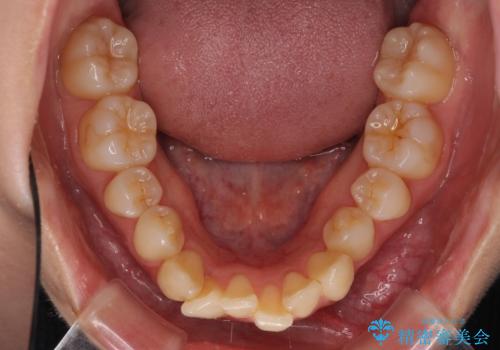

- 上の前歯、および下の歯列全体のでこぼこを気にして来院された患者様です。

インビザラインを用い、IPR(歯と歯の間を削る)と歯列全体を後方に移動させることで、歯並びを整えていくこととしました。

歯列全体を後方に移動させるため、下顎の親知らず2本を抜歯することとしました。